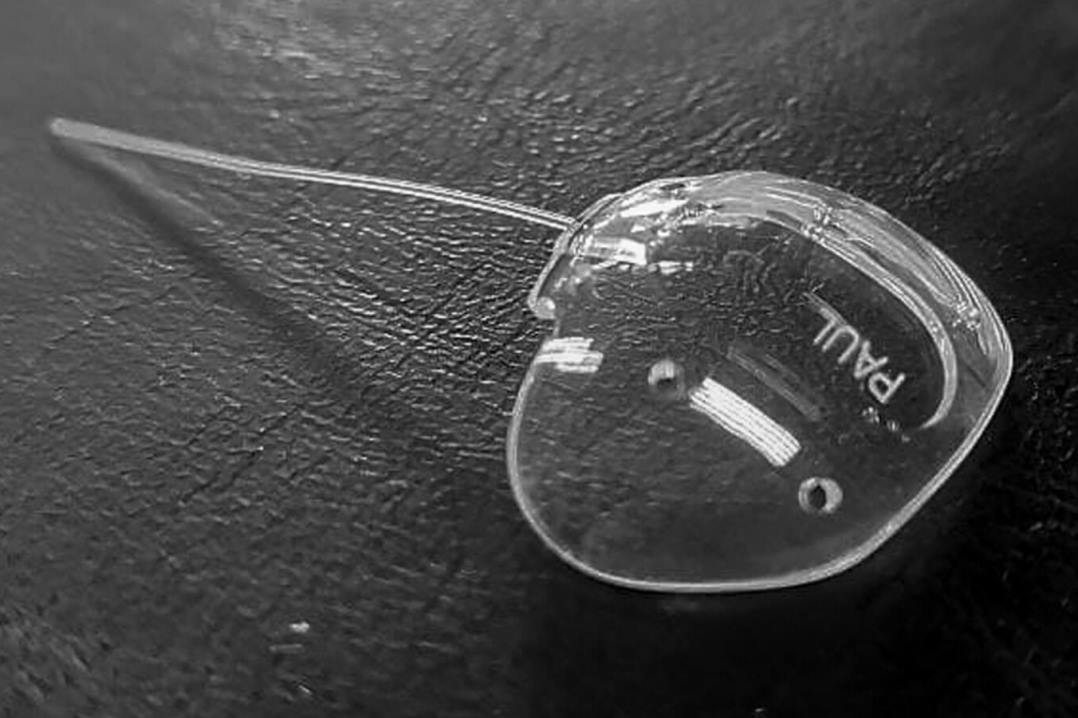

Infectious scleritis usually requires combined medical and surgical management, with only 1/5 responding to medical treatment alone. Both topical and oral antimicrobials directed towards the causative organism are needed and drug penetration is poor through the avascular sclera. Surgical management is important in providing a microbial diagnosis, debulking a scleral abscess, debriding necrotic tissue and removing any foreign bodies that may serve as a nidus for infection, such as a scleral buckle or glaucoma drainage device4.